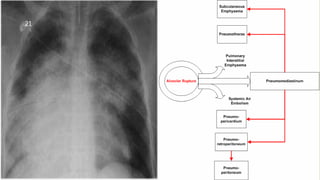

DAMAGE TO LUNGS DUE TO AIR BLAST

Alveolar haemorrhage due to tearing of

alveolar septa

Lungs are bruised due to direct blow on the

chest by bomb fragments and debris.

Chest X-ray showing typical bilateral patchy

infiltrates.

Commonly known as “Blast Lungs”

20

DAMAGE TO LUNGSDUE TO AIR BLAST Alveolar haemorrhage due to tearing of alveolar septa Lungs are bruised due to direct blow on the chest by bomb fragments and debris. Chest X-ray showing typical bilateral patchy infiltrates. Commonly known as “Blast Lungs” 20